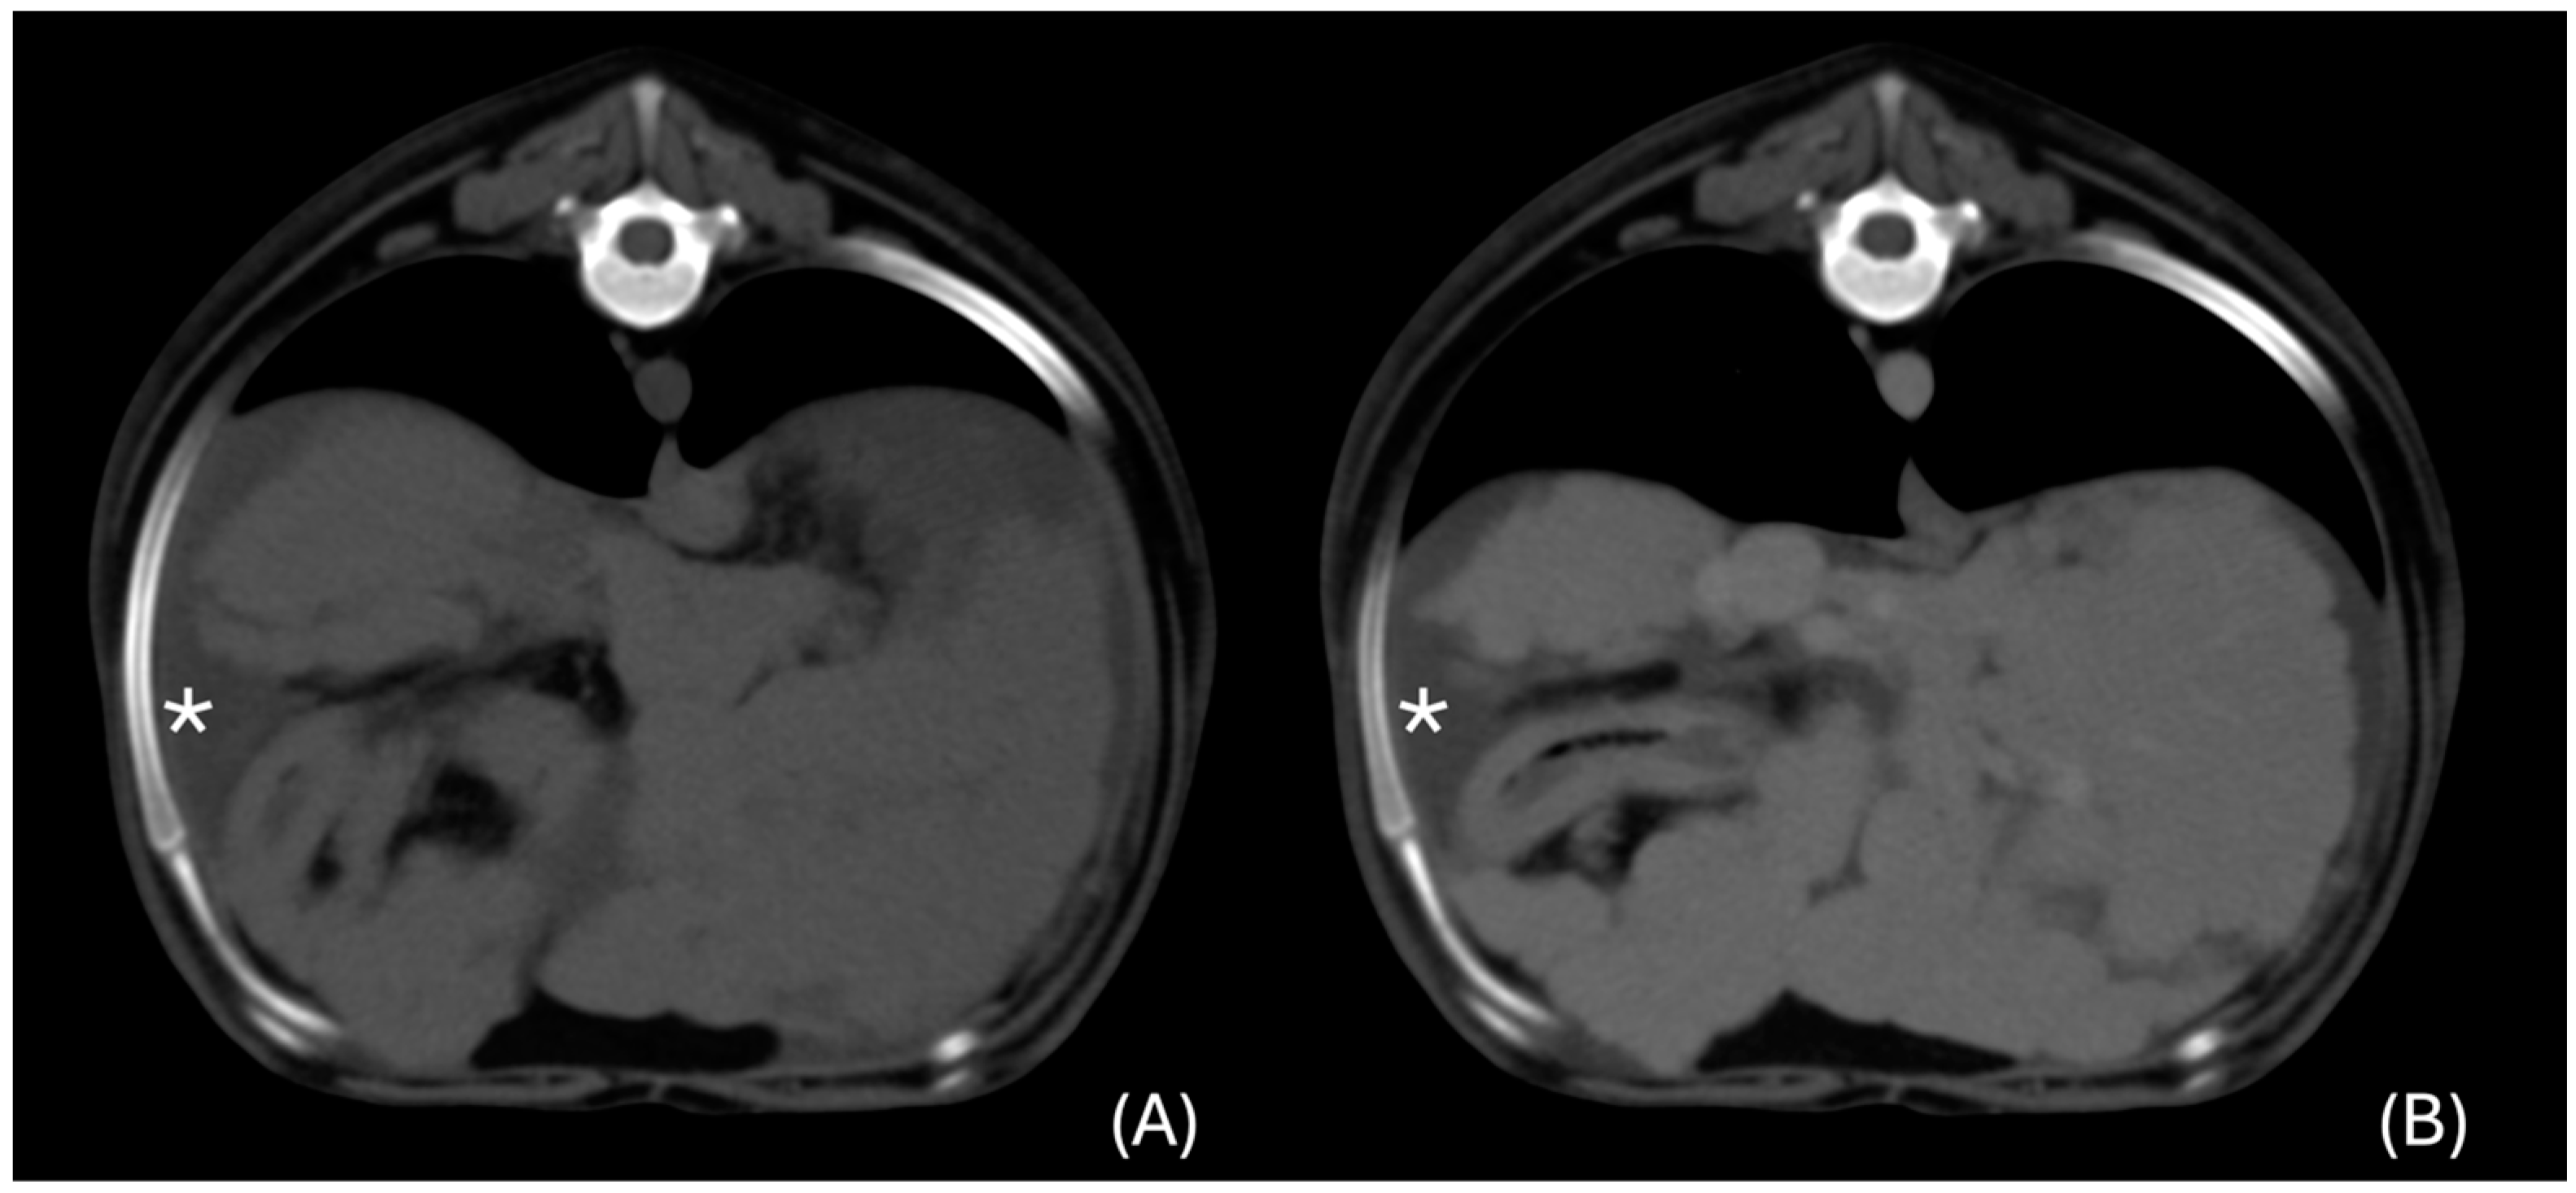

3.6.1. “Diffuse” Changes